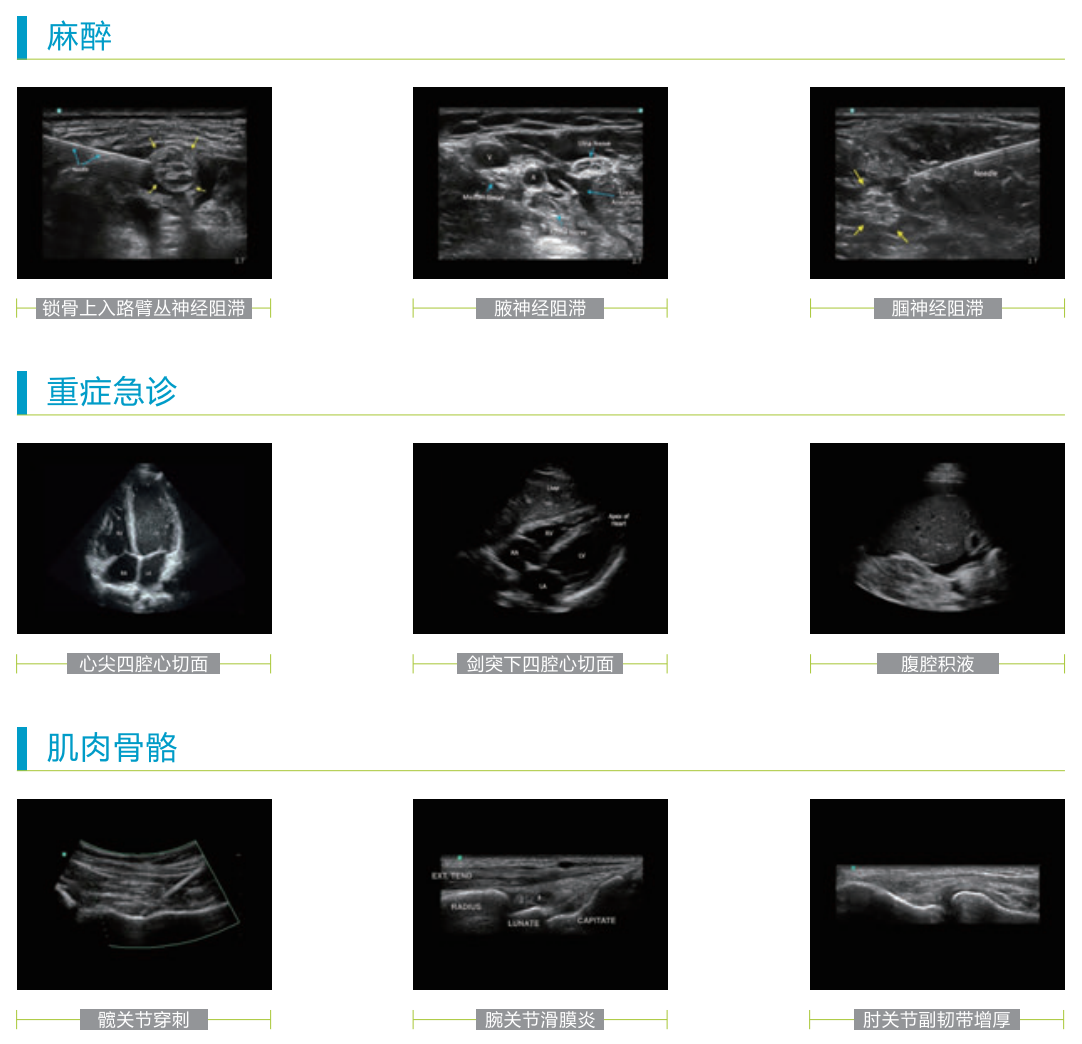

應用范圍

臨床醫(yī)生不可或缺的可視化工具

M-Turbo便攜式彩色超聲診斷系統(tǒng),可廣泛地應用于各臨床科室, 讓POC 可視化診療過程更便捷、更有效、更精確。

麻醉科、重癥科、急診科、超聲科、CVC、PICC、 泌尿科、肌肉骨骼、 心臟科、婦產(chǎn)科、外科、兒科、神經(jīng)科等各POC 臨床領域